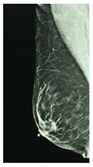

According to the Breast Imaging Data and Reporting System (BI-RADS), a PBD increase along a three-year period is associated with a higher breast cancer risk, and a PBD decrease with a smaller risk, than the risk when PBD remains unchanged. Two longitudinal BI-RADS breast density measurements (on current and previous mammography) may be better predictors of breast cancer risk than a single measurement [14]. The incorporation of breast density to the Gail model, a mathematical instrument that measures the risk of developing breast cancer in five years by identifying risk factors [15], increases predictive accuracy by statistical agreement from 0.607 to 0.642 [16]. The PBD BI-RADS classification is defined in Table 1, where illustrative cranio-caudal (CC) and mid-lateral oblique (MLO) mammography imaging samples for right and left breast are shown.

Table 1. BI-RADS classification and its relationship with mammography.

BI-RADS PBD ClassificationMammography

Right

(CCR)

Left

(CCL)

(MLOR)

(MLOL)

a = 0–25%

(Homogeneous adipose)

Sensors 22 02747 i001 Sensors 22 02747 i002 Sensors 22 02747 i003 Sensors 22 02747 i004

b = 25–50%

(Heterogeneous dispersed)

Sensors 22 02747 i005 Sensors 22 02747 i006 Sensors 22 02747 i007 Sensors 22 02747 i008

c = 50–75%

(Dense heterogeneous)

Sensors 22 02747 i009 Sensors 22 02747 i010 Sensors 22 02747 i011 Sensors 22 02747 i012

d = 75–100%

(Extremely dense)

Sensors 22 02747 i013 Sensors 22 02747 i014 Sensors 22 02747 i015 Sensors 22 02747 i016